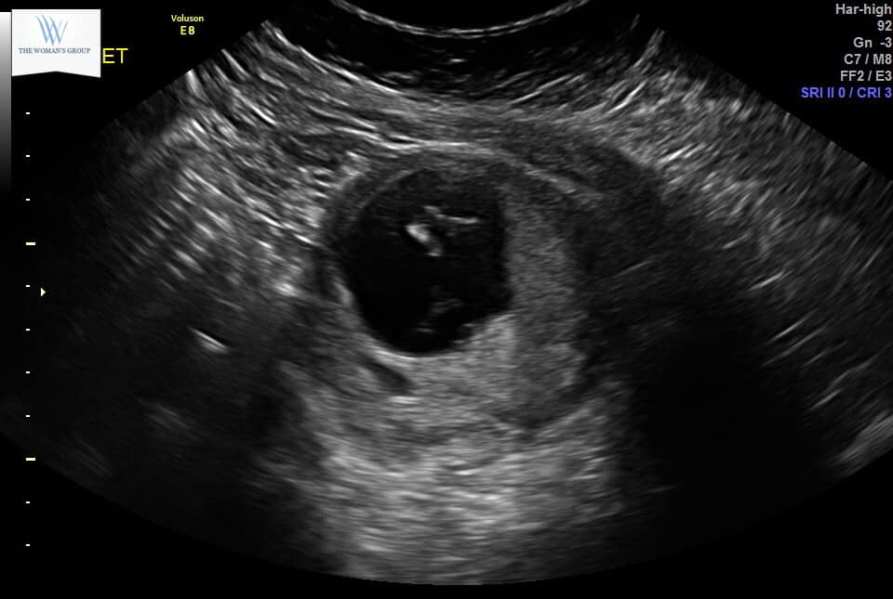

This blog began as a way for me to get my thoughts down on “paper.” Ill start with just a general introduction to my life and family. My name is Laura, I’m currently 29 years old, and 29 weeks pregnant. I am from Tampa, FL, but currently am living in Philadelphia Pennsylvania. (It’s a long story, bear with me..) I am one of four children, I have two triplet siblings, and a younger sister who showed up 3 years later. My parents are both alive and well, they are the exception to most marriages in that they have been hitched for 37 years and are still completely devoted and obsessed with one another. I come from a very large and blended Hispanic and Polish family, and I love them all to death. Ill probably throw in the occasional ethnic recipe in this blog for funsies, with the exception of my Cuban grandmother’s flan recipe, as that is a state secret that I am not privy to.